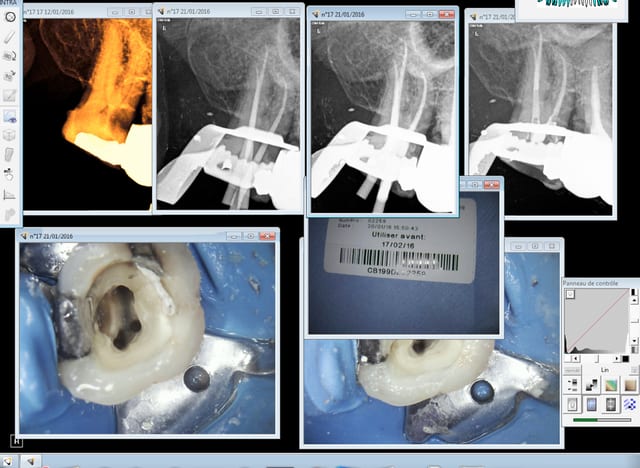

Sur TOUS mes actes il y a un contexte photo-radio d'enregistré, c'est un réflexe comme celui de mettre des gants.

Capture d e cran 2016 01 21 10.38 - Eugenol

> Sur TOUS mes actes il y a un contexte photo-radio d'enregistré, c'est un réflexe

> comme celui de mettre des gants.

Tu as une traçabilité avec code barre mais du coup tu prends en photo l'étiquette et tu scannes aussi le code barre avec une douchette ??

Photo ca suffit tu as le numero de cycle et 'autoclave enregistre les paramètres du cycle.